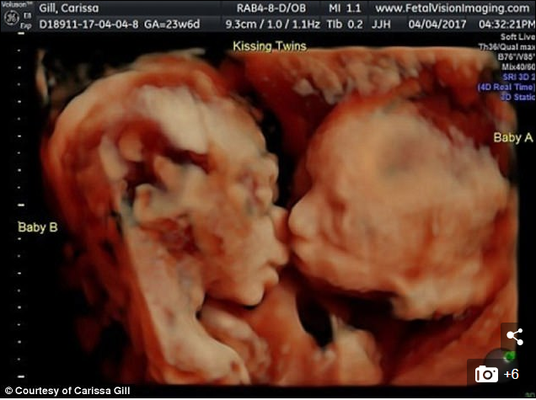

Uma imagem relata bem esse amor. O casal Carissa Gill e Randy Good, da Pensilvânia, Estados Unidos, realizava um ultrassom de rotina quando foram surpreendidos com a imagem de suas gêmeas com os rostos bem próximos, como estivessem se beijando.

John Hamburg, que realizava o exame, explicou que a posição em que as bebês estavam não é comum: “Já fiz mais de 15.000 exames desse tipo e nunca vi gêmeos com o rosto próximo desse jeito, parecendo que estão se beijando. Normalmente, um fica com a cabeça para cima e outro com a cabeça para baixo”, disse ao Huffington Post.

Apesar das dúvidas sobre a veracidade das imagens, o médico garantiu que a cena é legítima.

Veja mais fotos do Ultrassom de Carissa: